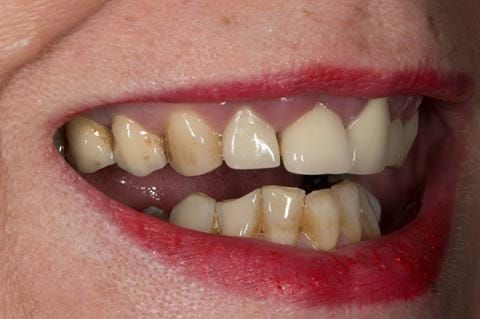

- High smile line showing gum above gingival zeniths of upper front teeth when smiling. Aesthetic failure of the upper four incisors with inflammation of the gingivae and mis-match of the gingival zenith levels.

- Other than the maxillary incisors the remaining dentition was in marginally better condition being moderately to heavily restored. Many will probably require replacement and restoration from time to time mainly from wear and tear owing to occlusal forces.